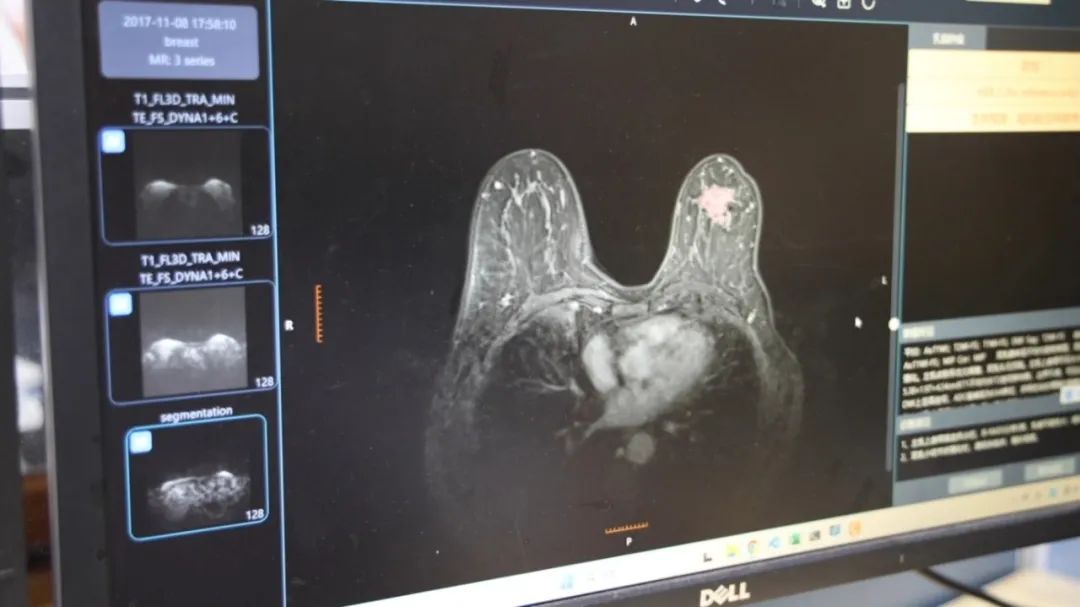

训练自全国三家医院5205名患者乳腺核磁共振数据,MOME大模型肿瘤良恶性判断准确率超90%,与5年经验以上放射科医师水平相当。

“这是世界上首个乳腺核磁共振多模态大模型。”陈浩介绍。“它能在无创前提下实现良恶性肿瘤精准分析,减少病理穿刺给病人带来的痛苦,加速临床诊疗时间。”

吴明祥补充道,一套乳腺核磁共振图像包含上千张图像,而MOME相当于为医生配备AI助手,辅助医生快速浏览核磁图像,缩短初筛时间,快速定位可疑病灶并定性分析。